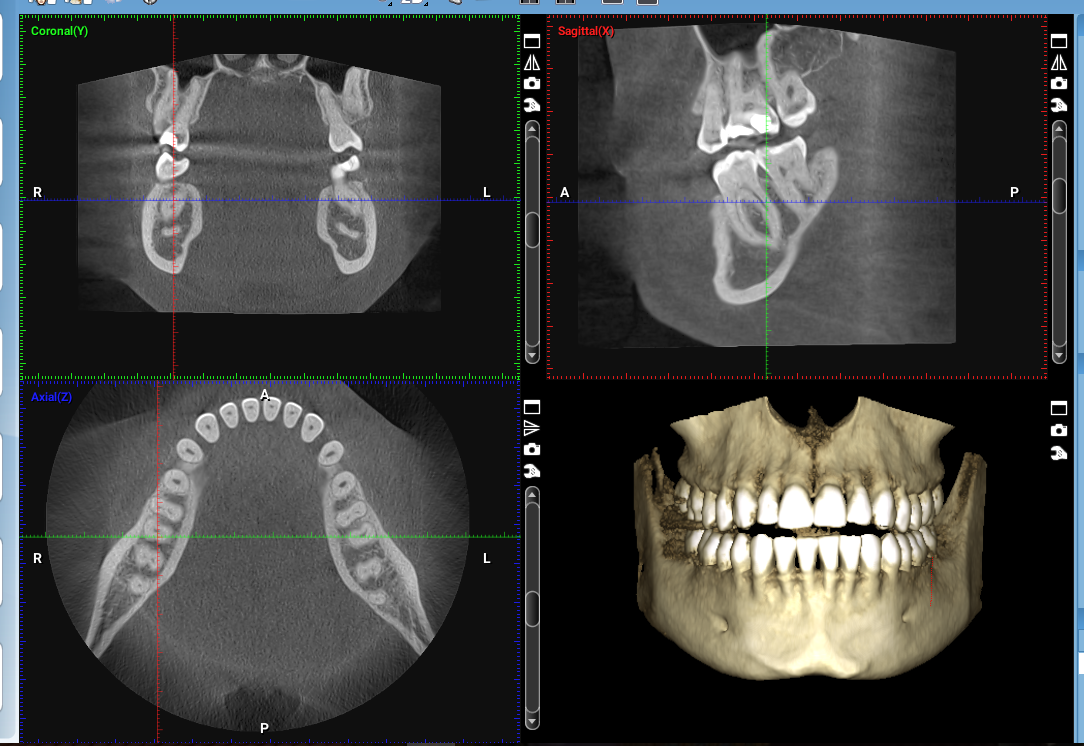

CBCT Applications in Dentistry 3D Sectional Images Processing and Interpretation

- Describe the principles of CBCT image production

- Identify the advantages, disadvantages, uses, and limitations of CBCT imaging

- Demonstrate reformatting and processing CBCT images using image processing software.

- Analyze the CBCT images of different cases efficiently.

- Demonstrate effective utilization of CBCT images to diagnose and plan treatment for a variety of dental conditions.